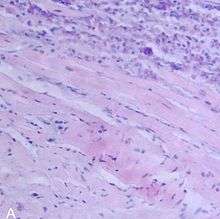

| A microscope image of myocarditis at autopsy in a person with acute onset of heart failure | |

The gold standard is still biopsy of the myocardium, in general done in the setting of angiography. A small tissue sample of the endocardium and myocardium is taken, and investigated by a pathologist by light microscopy and—if necessary—immunochemistry and special staining methods. Histopathological features are myocardial interstitium with abundant edema and inflammatory infiltrate, rich in lymphocytes and macrophages. Focal destruction of myocytes explains the myocardial pump failure.[8]